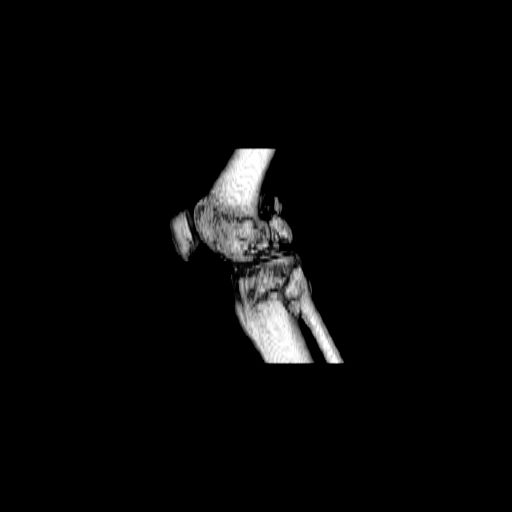

При внутрисуcтавных переломах трехмерные (3D) изображения, кроме красивого снимка, не дают полную информацию о состоянии отломков, самыми информативными являются корональные срезы на КТ и обычная длинная ренгенограмма конечности для сравнения оси конечности.

Фронтальные внутрисуставные переломы мыщельков бедра, так называемые Hoffa fracture, не частые, но встречающиеся переломы, в основном они связаны с травмой высокой энергией.

В зависимости от смещения рекомендуется сопоставление костных фрагментов с последующей жесткой фиксацией.

В вашем случае доступ будет медиальный, сопоставить развернутый медиальный мыщелок и фиксацию надо произвести в передне-заднем

направлении шурупами 4.5 мм в диаметре, углубив головку шурупов под хрящ, а поперечную фиксацию - межмыщелковыми шурупами. Желательно применить шурупы 6.3 мм в диаметре. Дополнительная Buttress technique пластина предотвратит перелом от скольжения.

Даже при сросшемся переломе мыщелка рекомендуется реконструктивная операция для предотвращения последующих варус или вальгус деформации.

Место образовавшего костного дефекта после разворота мышелка заполняется спонгиозной аутокостью. Костная пластика применяется даже

в свежем случае.

Под наркозом редрессация, ранняя разработка сустава после операции, нагрузка на конечность через 12 недель помогут удержать без коллапса

фиксацию и поможет больному восстановить функции конечности без артропластики коленного сутава.